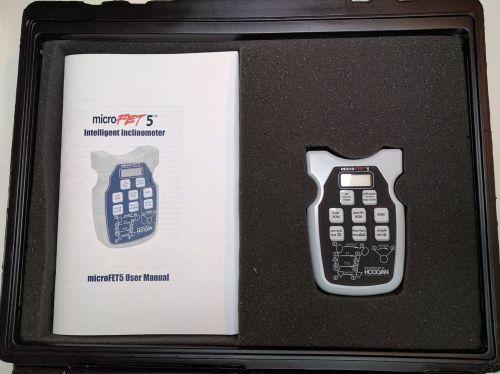

MICROFET 5 INTELLIGENT SINGLE INCLINOMETER - HOGGAN HEALTH